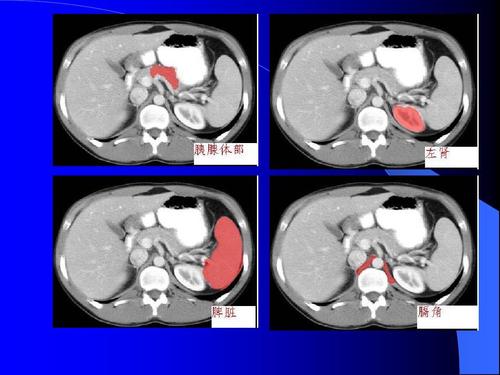

2.1将两种诊断结果与术中和术后病理结果进行对比,准确率为93.3%(56/60),超声检查准确率为78.3%(47/60)。差异有统计学意义(P2。腹部闭合性损伤诊断结果的2CT分析结合美国创伤外科学会器官损伤分类标准和[3号腹部闭合性损伤中脾、肝、肾损伤60例,其中脾损伤24例:ⅰ级8例,ⅱ级12例,ⅲ级4例。肝损伤19例:ⅰ级7例,ⅱ级3例,ⅲ级4例,ⅳ级5例。肾损伤7例:ⅰ级损伤3例,ⅱ级损伤2例,ⅲ级损伤2例。其余5例为空肠破裂,4例胃损伤,1例胰腺损伤。

随着交通事故和其他意外伤害发生率的增加,临床腹部闭合性损伤的发生率也显著增加。近年来,研究发现,这种疾病已经成为[3]急诊患者死亡的主要原因之一。腹部闭合性损伤主要包括空腔器官损伤和实质性器官损伤。胃肠道和胆囊属于空腔损伤,腹膜炎是主要临床表现。

肝、脾、肾等。是实质器官损伤,主要是出血。早期诊断和及时治疗是挽救病人生命的关键。临床腹部闭合性损伤通常由超声和计算机断层扫描诊断。超声检查因其成本低、操作简单、对患者无创伤等优点,在临床上得到广泛应用。然而,近年来的相关研究结果表明,超声检查方法更易受体位、胃肠蠕动等因素的影响,因此临床诊断准确性与[4号相比并不理想。

从本研究结果来看,CT诊断的准确率为93.3%,明显高于超声诊断的准确率(78.3%) (p综上所述,腹部闭合性损伤的CT检查的临床准确率相对较高,可以在不受受体部位等因素干扰的情况下对患者的损伤进行初步分级,可以为临床治疗和诊断提供必要的参考校正,值得临床推广。(省略)